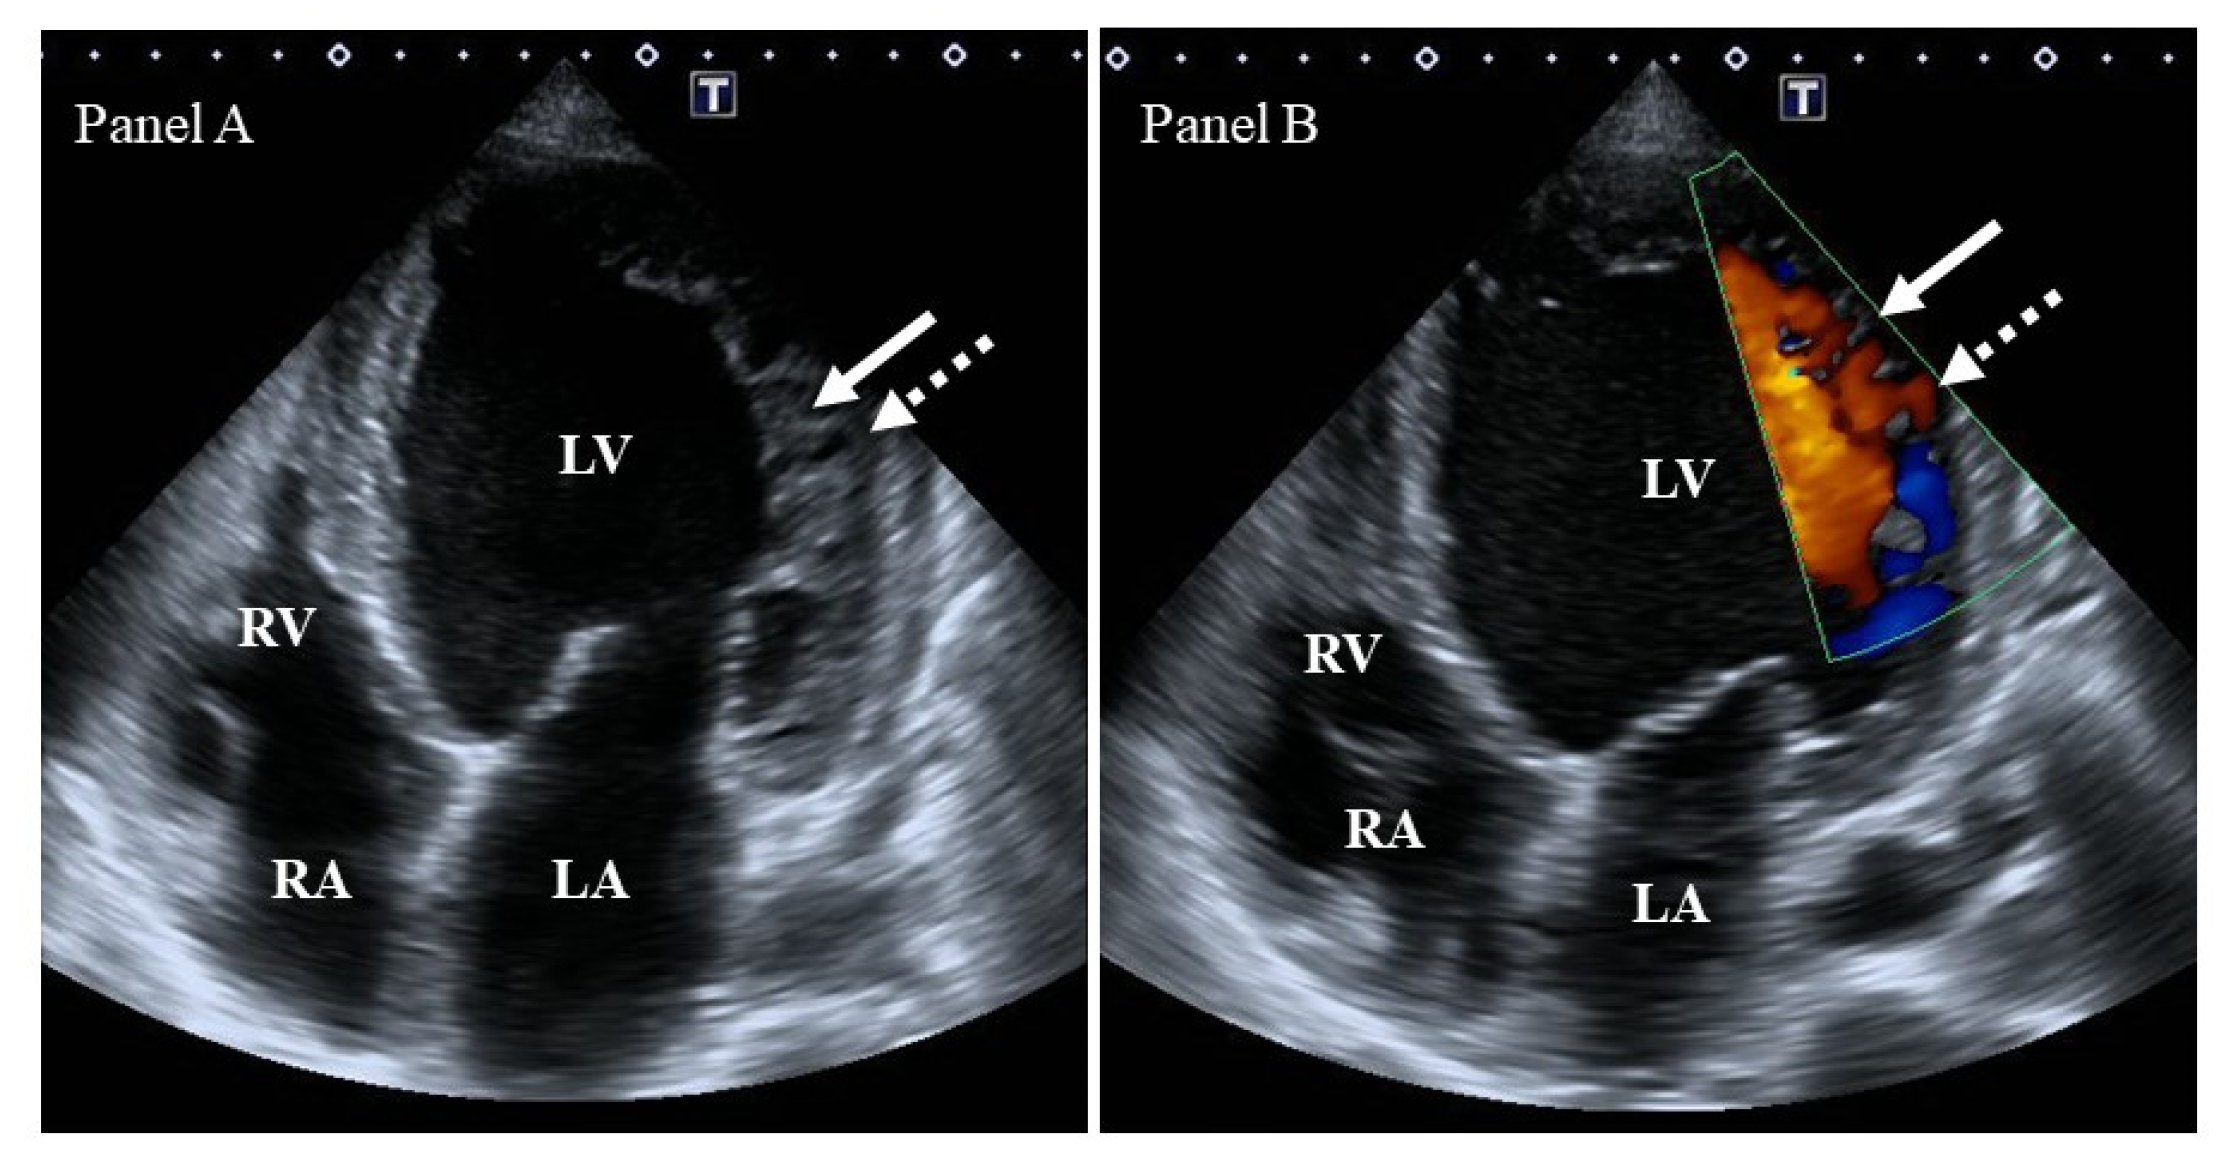

Pseudoaneurysm

What is seen in the 2D image?

A saccular outpouching with a narrow neck originating from a discontinuity in the heart wall.

Narrow neck and lack myocardial or endocardial tissue.